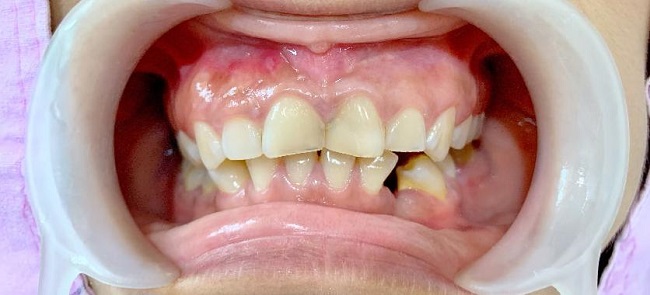

Khớp cắn chéo là tình trạng các răng cửa hoặc răng hàm không căn chỉnh đúng vị trí khi cắn chặt hai hàm. Thay vì các răng hàm trên phủ lên các răng hàm dưới một cách phù hợp, chúng lại bị lệch hoặc chéo sang bên trong hoặc bên ngoài, gây mất thẩm mỹ, khó khăn trong việc ăn nhai và các vấn đề khác về sức khỏe răng miệng.

- Răng bị lệch sang một bên hoặc phía trong phía ngoài so với răng đối diện

- Lệch mặt hoặc biến dạng khuôn mặt

Tác động đến thẩm mỹ khuôn mặt

Biểu hiện rõ rệt qua khuôn mặt lệch, cằm không cân đối, ảnh hưởng đến tự tin.